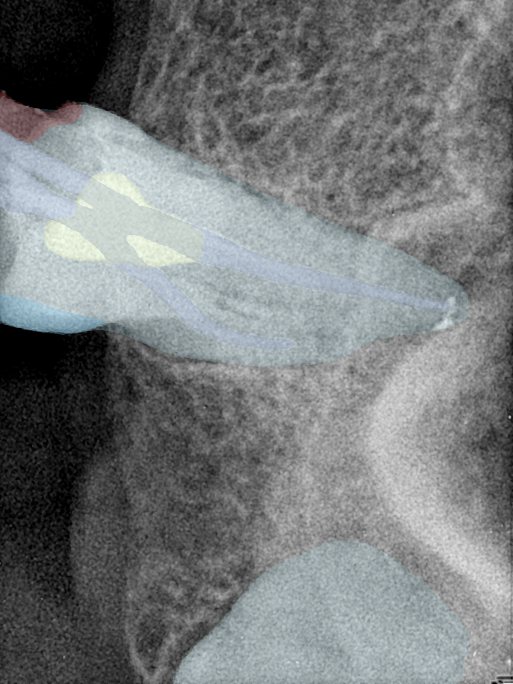

第三版算法分辨率效果比较

Updated: 2026-04-13(更新日期)

| 编号 | 原图 | 第一版 | 第二版 | 第三版 1216x1600 | 第三版 768x1024 | 第三版 1120x1120 |

|---|---|---|---|---|---|---|

| 131315.jpg | ![]() | ![]() | ![]() | ![]() | ![]() | ![]() |

| 131316.jpg | ![]() | ![]() | ![]() | ![]() | ![]() | ![]() |

| 131317.jpg | ![]() | ![]() | ![]() | ![]() | ![]() | ![]() |

| 131318.jpg | ![]() | ![]() | ![]() | ![]() | ![]() | ![]() |

| 131319.jpg | ![]() | ![]() | ![]() | ![]() | ![]() | ![]() |

| 131320.jpg | ![]() | ![]() | ![]() | ![]() | ![]() | ![]() |

| 131321.jpg | ![]() | ![]() | ![]() | ![]() | ![]() | ![]() |

| 131326.jpg | ![]() | ![]() | ![]() | ![]() | ![]() | ![]() |